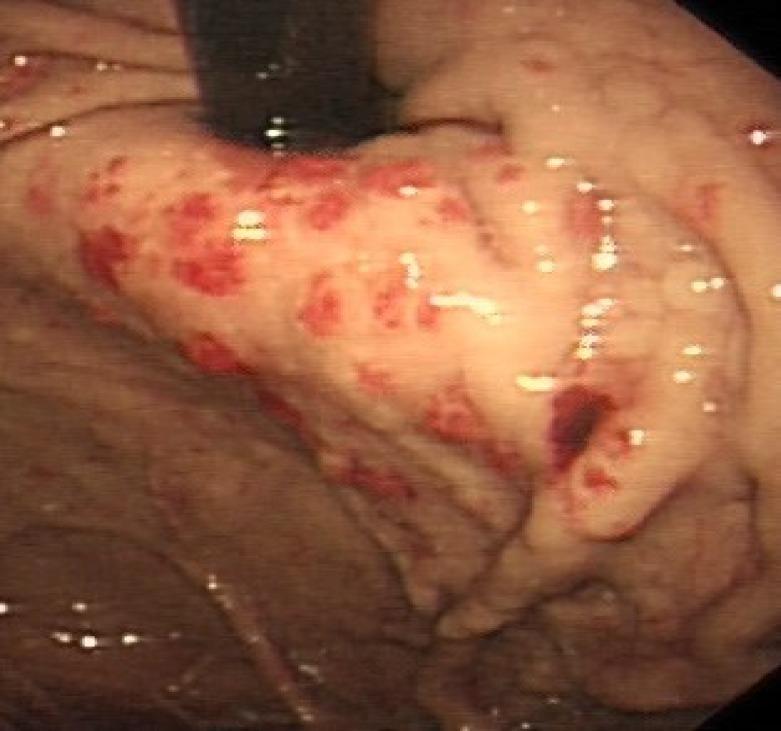

Chauhan Himadri, Mathews Sherly, Rostami Kamran

Department of Gastroenterology Milton Keynes University Hospital, United Kingdom.

Gastroenterol Hepatol Bed Bench. 2016 Summer;9(3):232-6.